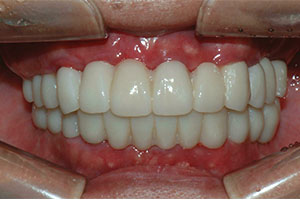

치료증례 전후사진

Before & After